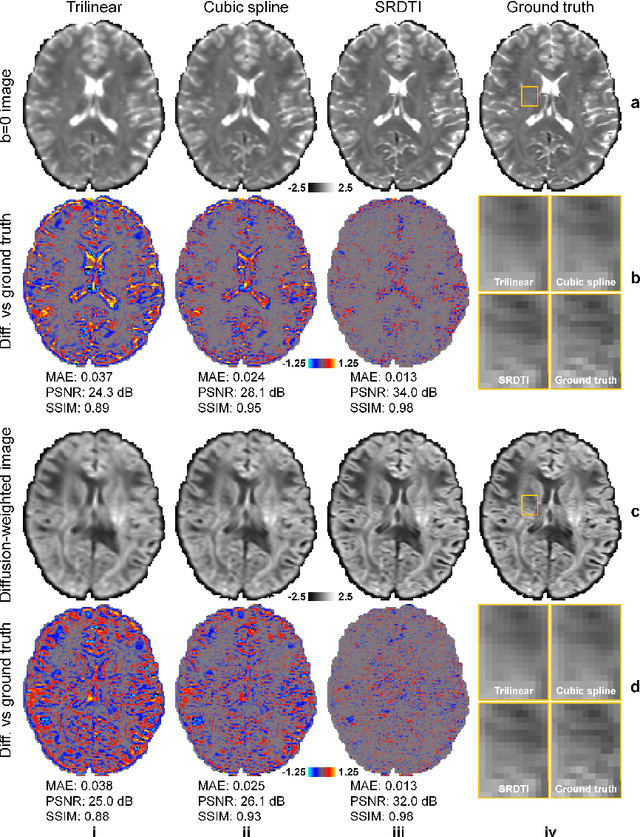

Abstract:High-resolution diffusion tensor imaging (DTI) is beneficial for probing tissue microstructure in fine neuroanatomical structures, but long scan times and limited signal-to-noise ratio pose significant barriers to acquiring DTI at sub-millimeter resolution. To address this challenge, we propose a deep learning-based super-resolution method entitled "SRDTI" to synthesize high-resolution diffusion-weighted images (DWIs) from low-resolution DWIs. SRDTI employs a deep convolutional neural network (CNN), residual learning and multi-contrast imaging, and generates high-quality results with rich textural details and microstructural information, which are more similar to high-resolution ground truth than those from trilinear and cubic spline interpolation.